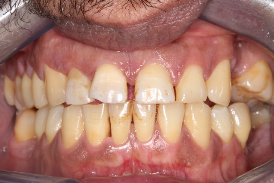

Pre-operative photo and X-ray